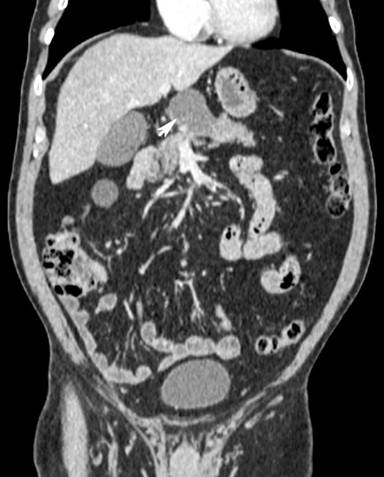

A 67-year-old man presented to the urologists with recurrent episodes of painless haematuria on the background of benign prostatic hypertrophy. An abdominal ultrasound scan demonstrated an incidental finding of a 5.7×4.7×4.4 cm thick walled avascular cystic structure with a thick septum in relation to the neck of the pancreas (Figure 1). Contrast enhanced computed tomography (Figure 2) confirmed the presence of a cyst related to the junction of the head and neck of the pancreas with otherwise normal architecture of the pancreas and no evidence of metastatic disease.

Figure 2. CT image of cyst (arrow) arising from the junction of the head and body of the pancreas. |